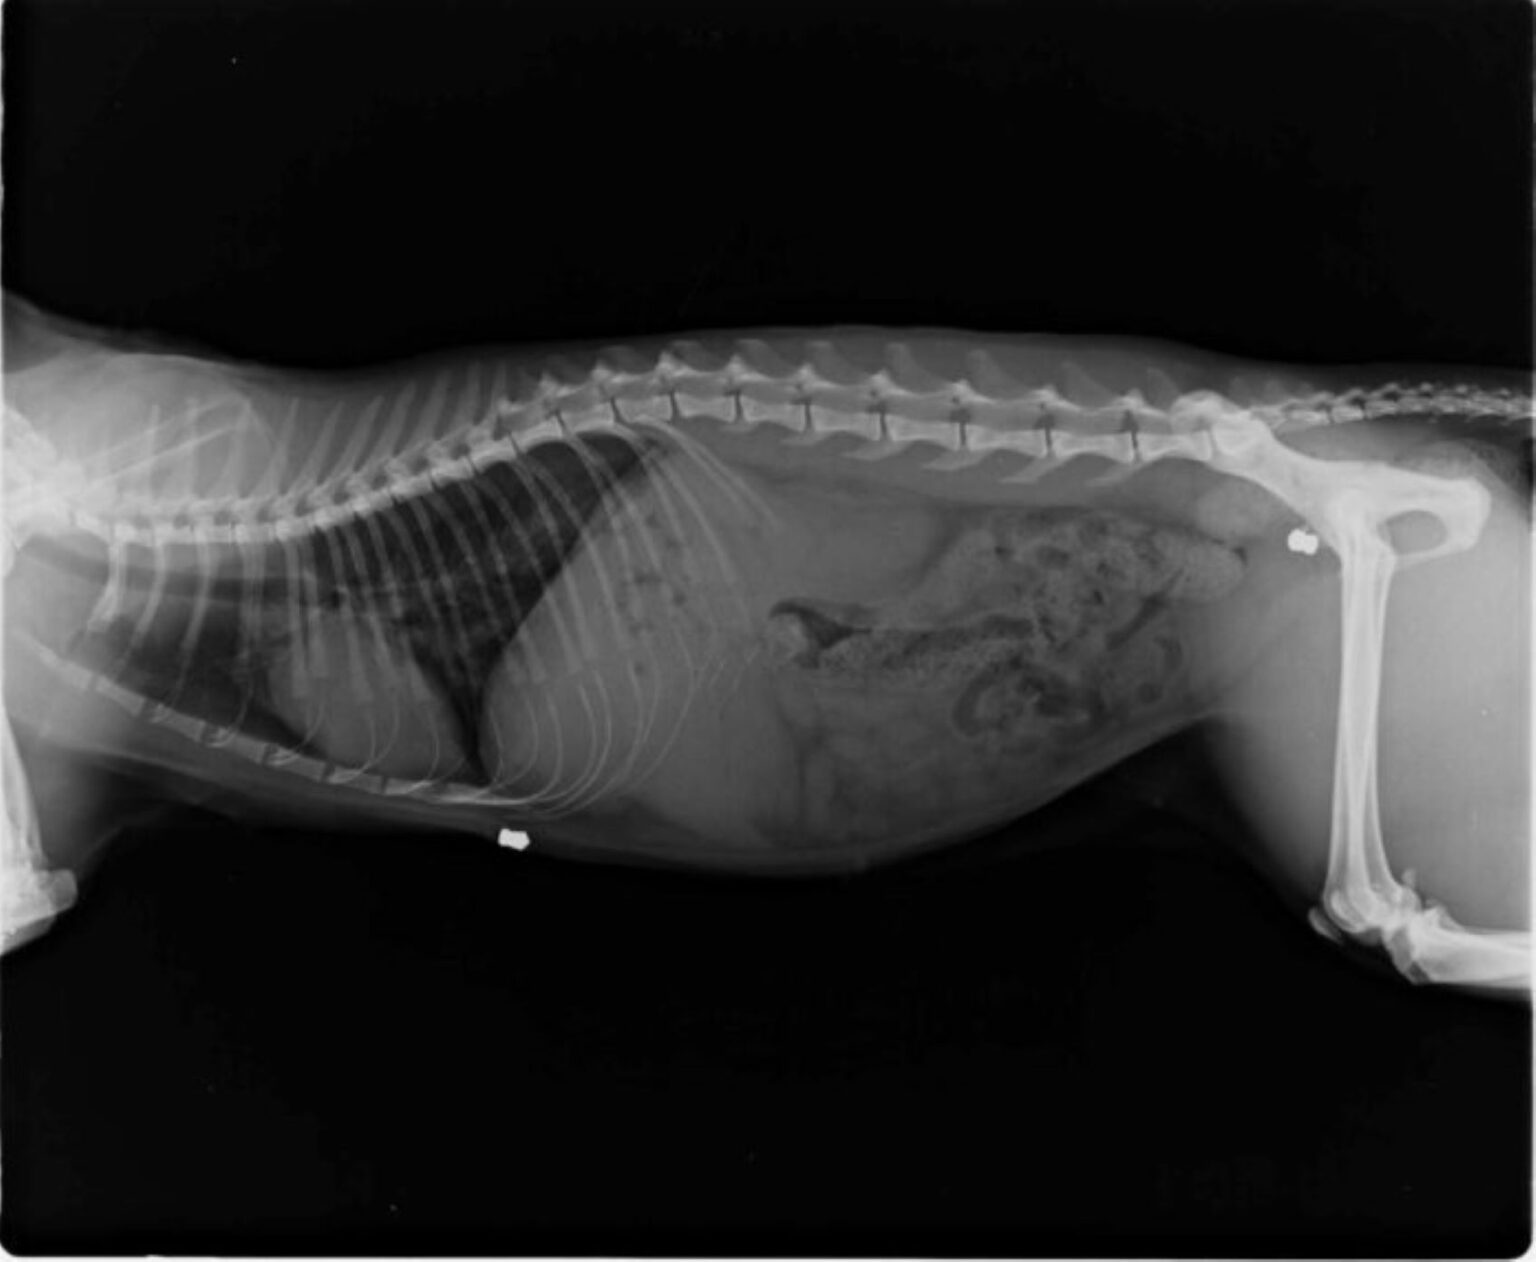

Κτηνωδία στην Εύβοια: Άγνωστοι πυροβόλησαν το σκυλί – μασκότ της Κύμης.

Εικόνα

Περισταστικό κακοποίησης ζώων καταγράφηκε χθες, Πέμπτη (29/6) στην Εύβοια και πιο συγκεκριμένα στην Κύμη, όπου άγνωστοι πυροβόλησαν το «σκυλί – μασκότ» της περιοχής το οποίο λάμβανε την αγάπη και τη φροντίδα των κατοίκων.

Σύμφωνα με τα τοπικά μέσα ενημέρωσης, όπως το eviathema.gr, διαπιστώθηκε το πρωί της Πέμπτης ότι το μικρό ζωάκι έφερε τραύματα με αίμα. Είχε προηγηθεί, όπως αναφέρεται, επιχείρηση για την ακινητοποίηση του σκύλου κοντά σε παιδική χαρά στην πλατεία Κύμης.

Μεταφέρθηκε στον κτηνίατρο – Φέρει βαριά τραύματα.

Το σκυλάκι μεταφέρθηκε σε κτηνιατρείο όπου διαπιστώθηκε πως φέρει βαρύ τραύμα από πυρά σε θώρακα και πόδια. Για αυτό το λόγο, μάλιστα, υπεβλήθη σε επέμβαση αλλά δεν κατέστη εφικτό να αφαιρεθεί η σφαίρα ενώ εκτιμάται πως θα αποβληθεί από τον οργανισμό του.

Τα τραύματα του δέχθηκαν φροντίδα και χρειάστηκε να κάνει συνολικά 14 ράμματα, δέκα στο μεγαλύτερο τραύμα και 4 στο μικρότερο. Η κατάσταση του ζώου κρίνεται αυτή την ώρα καλή και οι πολίτες ζητούν όσες είναι δυνατόν περισσότερες πληροφορίες για το συμβάν.

Οι άνθρωποι που το βρήκαν και το μετέφεραν στον κτηνίατρο έχουν δώσει κατάθεση στην αστυνομία και ο φάκελος θα πάει στον εισαγγελέα.